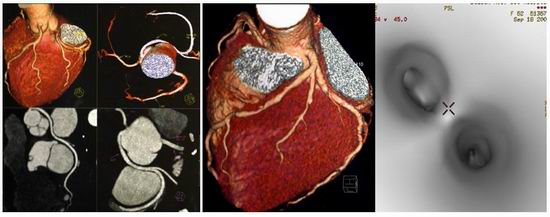

主要功能:Aquilion One是东芝新型0.35秒/320层/360度动态容积扫描CT,采用Volumexact+算法、TCOT算法、新型重建模块,为临床提供任何方向更清晰准确的三维图像。特别适合外伤一站式检查、神经系统和心脏的检查的快速检查要求,可以得到纯动脉和纯静脉成像。揭开了新的应用领域,尤其在动态容积成像和运动系统成像。